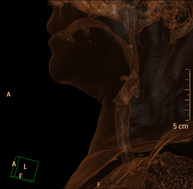

- Neck CT

Radiological test that provides high definition anatomical images of the neck using CT (Computed Tomography) equipment. Indicated for: thyroid study, control of treated tumours, study of lymph nodes, infections and abscesses.